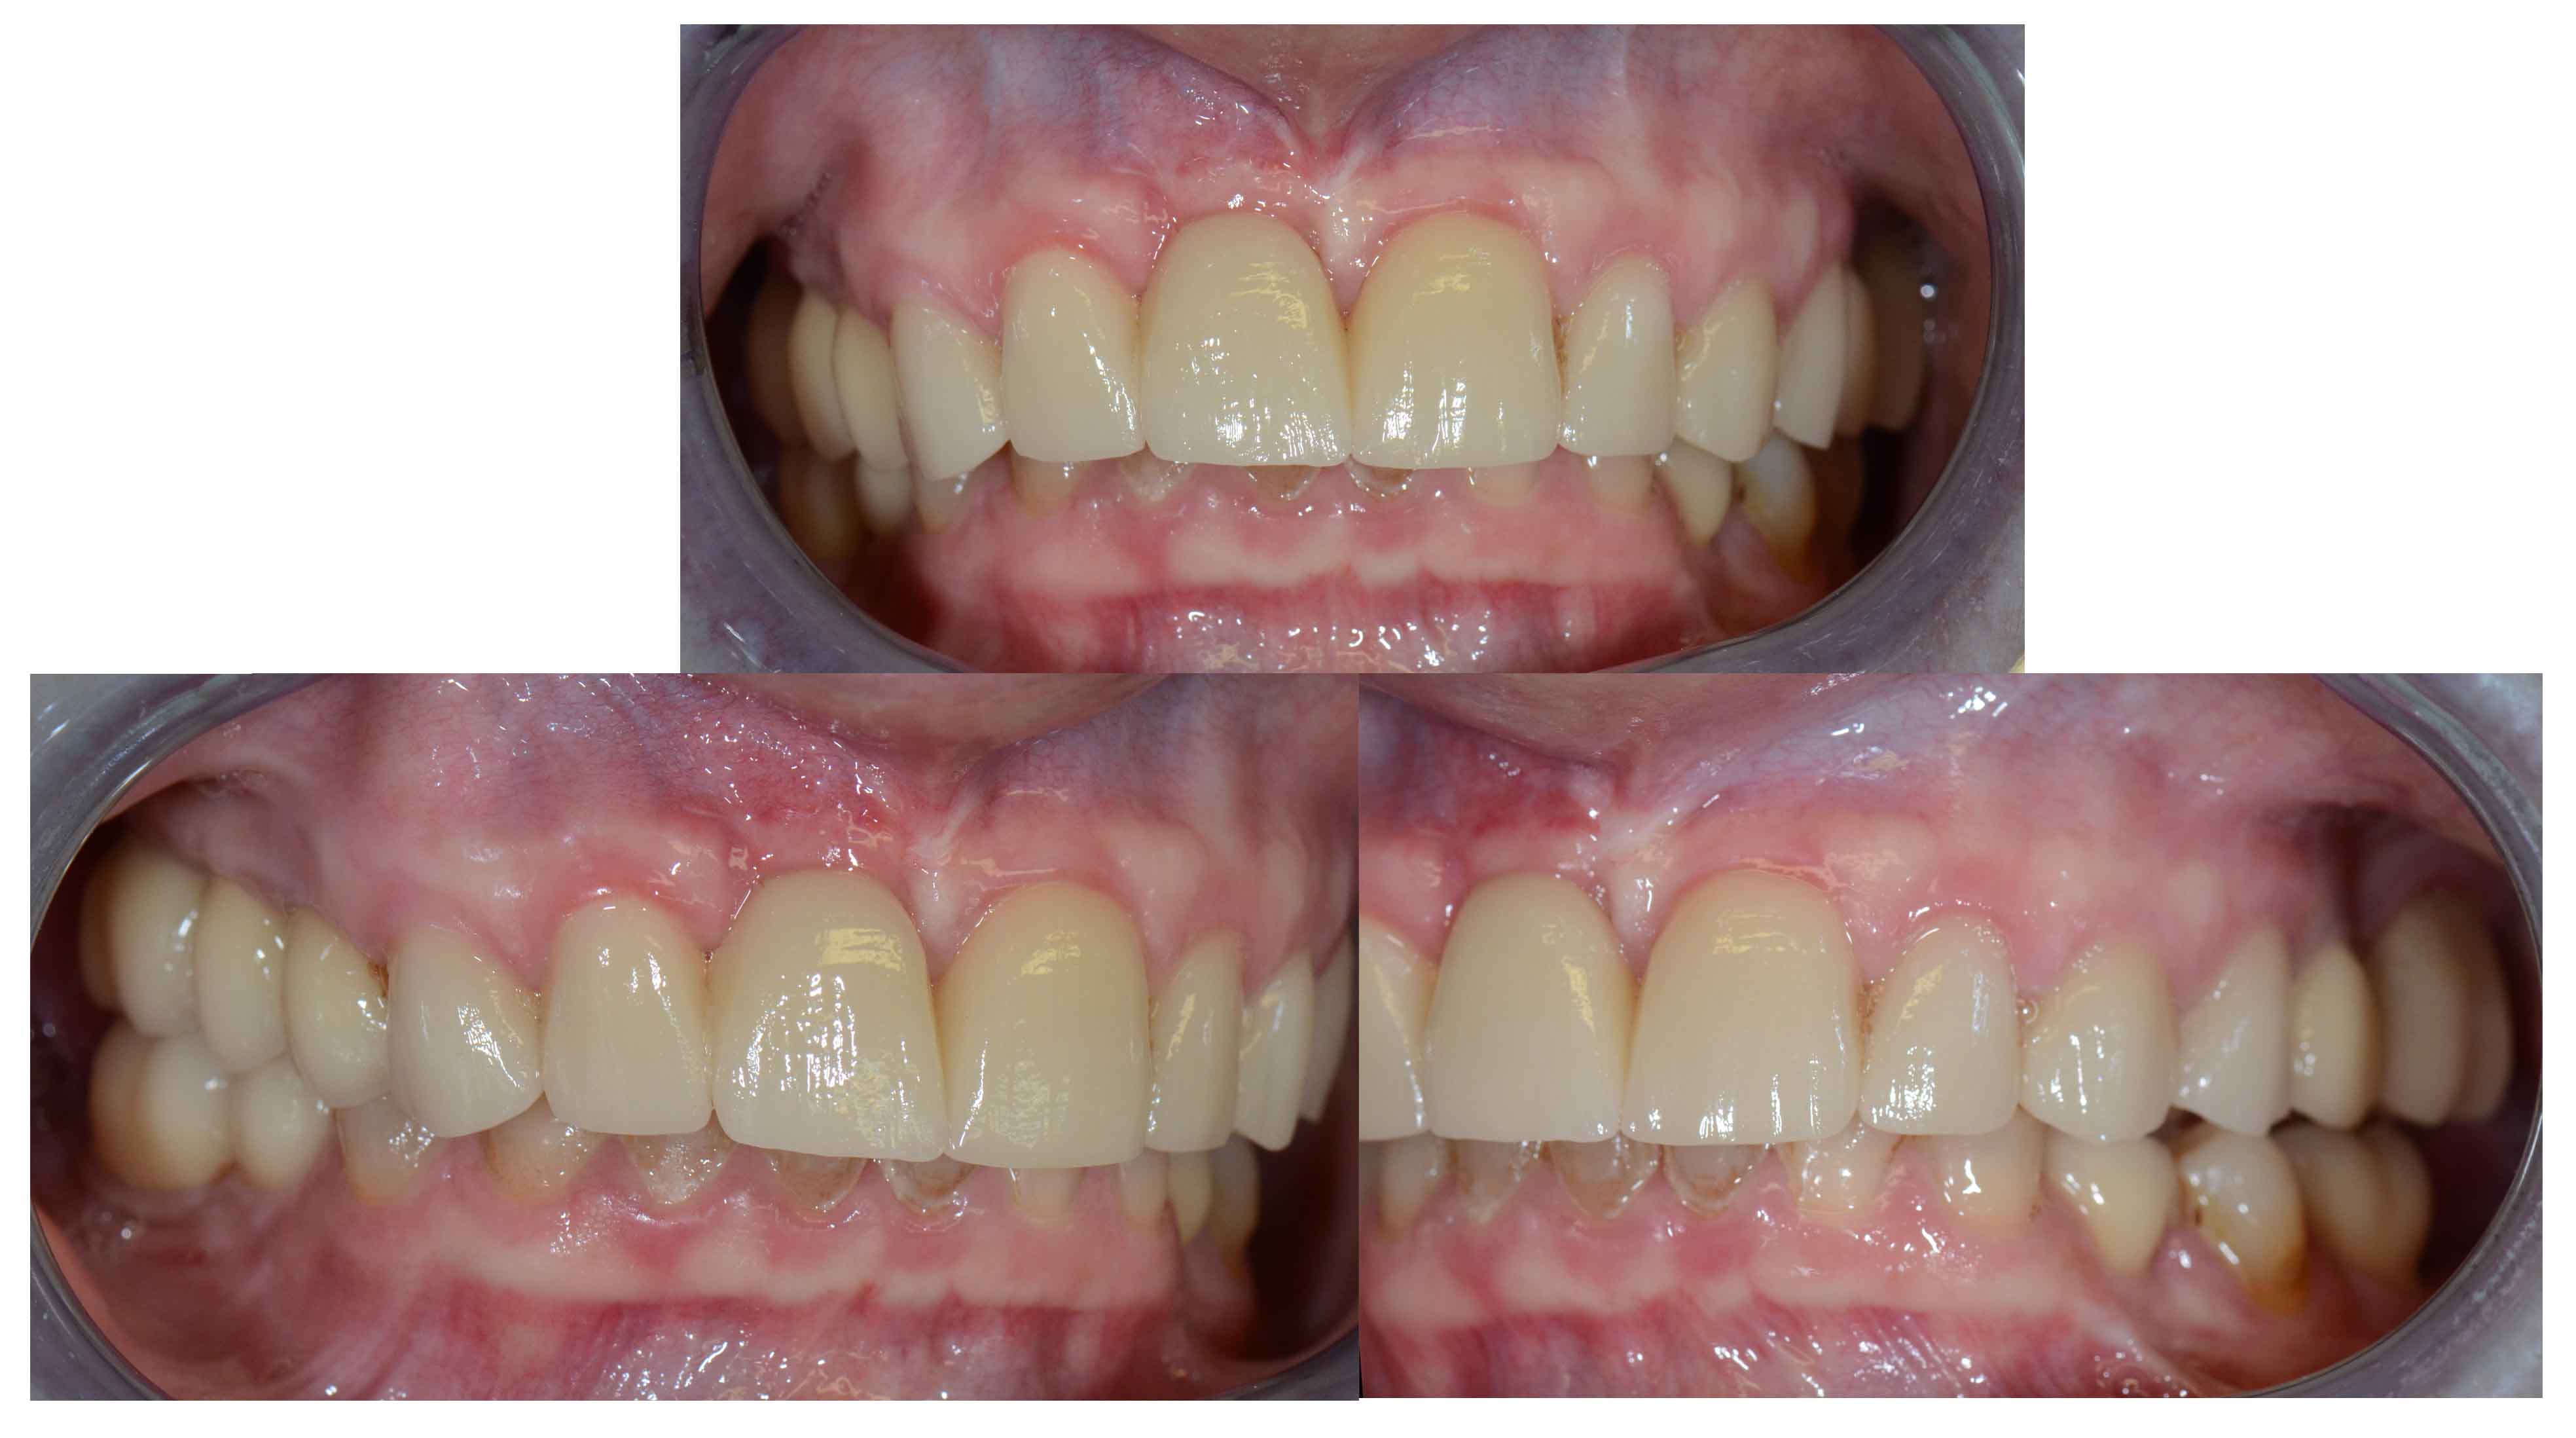

Tooth discoloration caused by tetracyclines

Aesthetic Rehabilitation with ceramic crowns and venners

Main problem:

Colour changes due to the use of tetracyclines as a child. Various treatments were done before to try to solve the problem but all of them were unsuccessful.

The Treatment:

Full crowns were opted to cover the teeth that were very damaged and venners were used to cover those who were less damaged and by doing this less natural tooth structure was damaged.